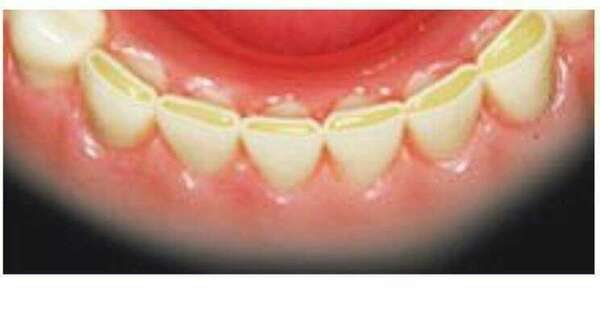

les restauration sur dents vivantes,

* des atteintes débutantes, par un matériaux inséré en phase plastique: le composite

* des atteintes plus volumineuses, par un matériaux rigide, réalisé sur empreinte: onlay et couronne sur dent vitale

* le renforcement de la dent dévitalisée par un faux moignon métallique ou fibré.